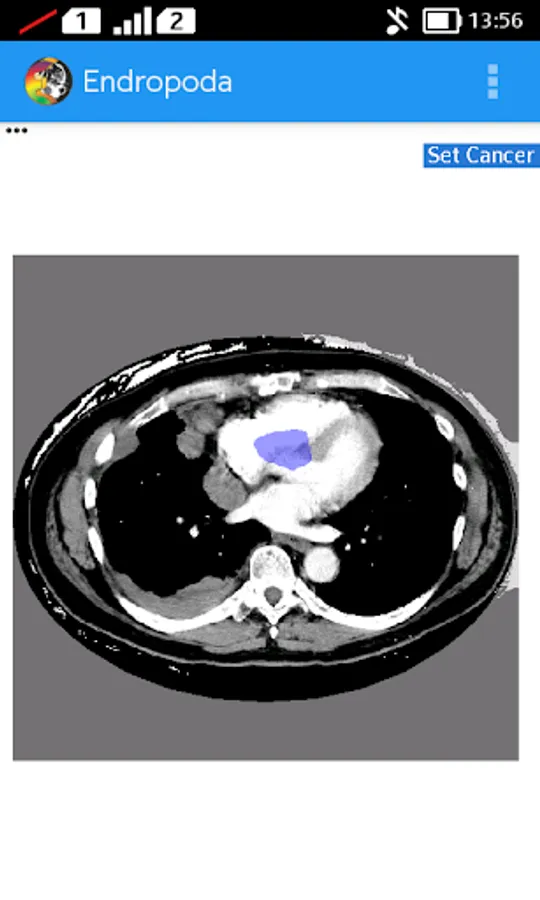

- Planning : In planning mode, user can create a region of interest on CT-Scan image to eliminate the background area and also can create cancer area that will be treated with radiation